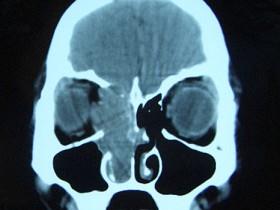

女,16岁,鼻塞、流涕一年余,失去嗅觉,影像检查如图所示,最可能的诊断是 ( )

答案: E